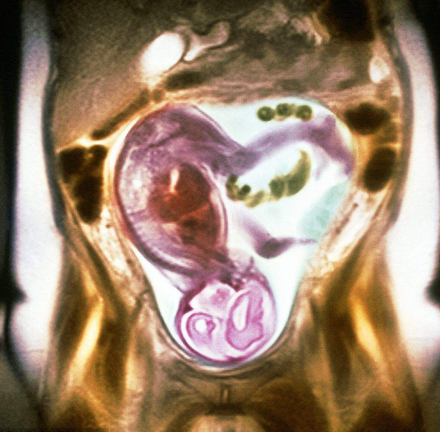

胎儿磁共振(MRI)的优势

不存在电离辐射;软组织分辨率高;视野大,可以任意切面扫描,显示胎儿全貌;受母亲情况影响小;不受胎儿骨骼及羊水量影响;对胎儿中枢神经系统疾病、羊水过少相关疾病和胸部疾病诊断方面有很高的准确性,在其他部位图像有良好的直观性和分辩率,并能量化评价肺发育不良。对于双胎及孕周较大时影像显示明显优于超声检查,特别是孕晚期胎头入盆或胎儿颅骨骨化时;胎儿 MRI 可进行任意切面扫描,精确地进行各种测量,对于胎儿疾病的定性较好,还可进行功能成像如磁共振波谱成像(MRS);MR 图像受检查操作者技术水平影响较小,便于保存和会诊。